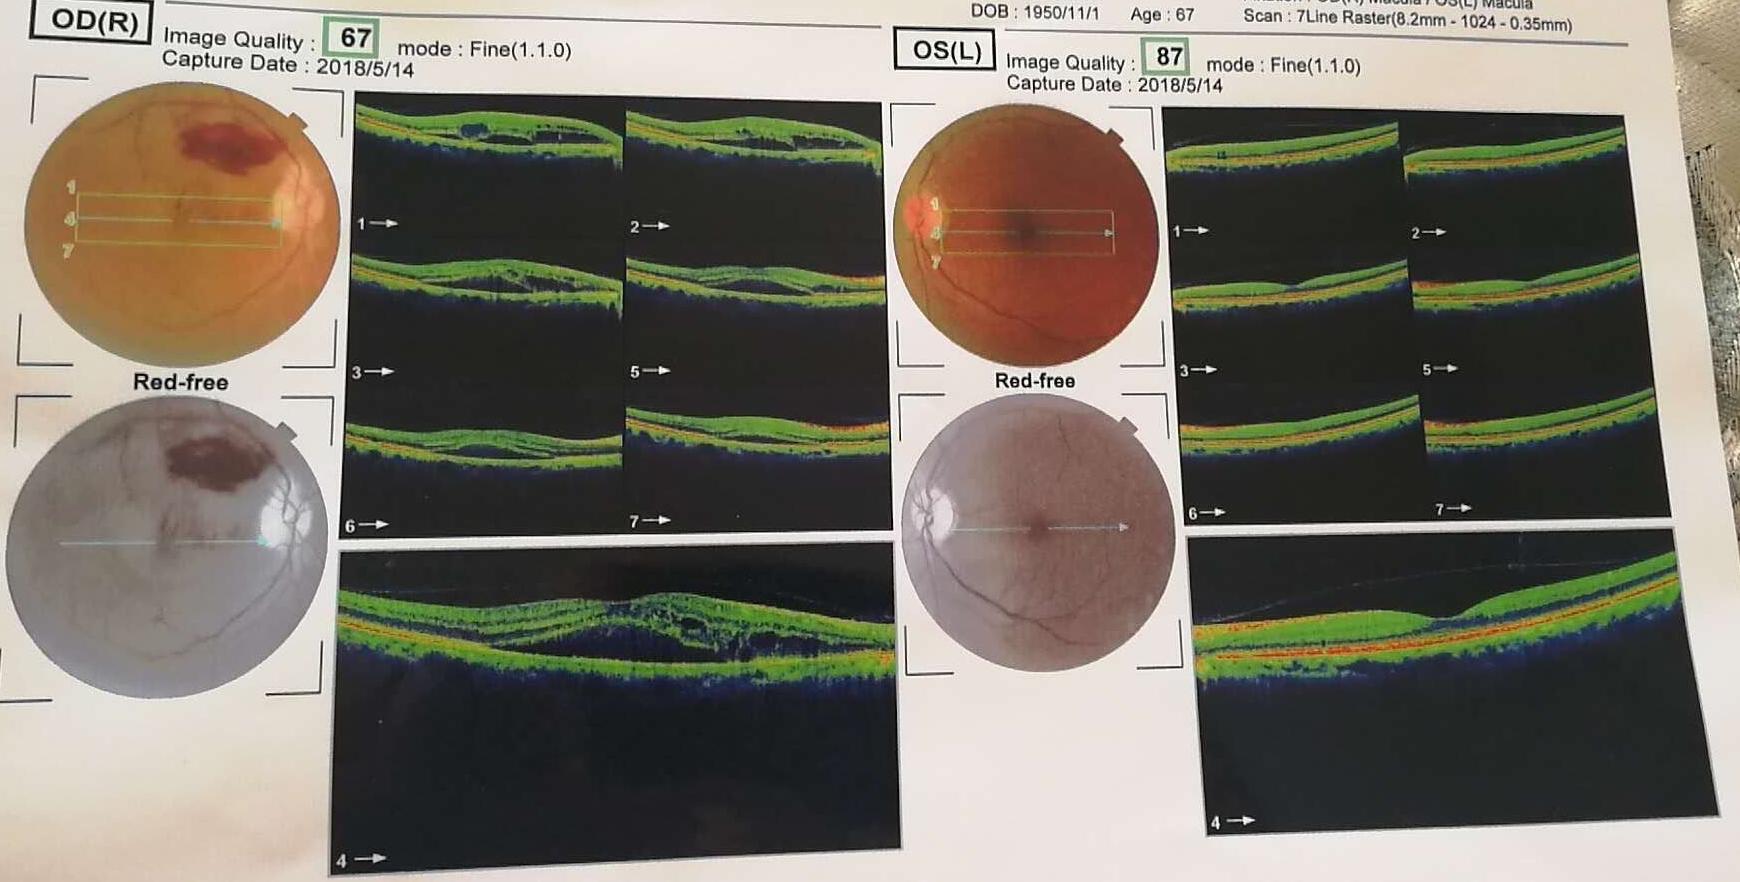

眼底水肿图片大全大图

眼底水肿图片大全大图,眼睛水肿图片大全大图

发病后可引起视力下降,视野缺损,一般缺血会导致黄斑水肿,眼底检查

fuchs斑phpvpcv晚霞状眼底 danen fuchs结黄斑囊样水肿 劈裂糖网性视

眼底水肿图片

眼底图片

眼底黄斑图片

眼底黄斑病图片

眼底图片解读

眼底图片解读结构图

眼底检查报告单图片

不正常的眼底照片

如何看眼底照相图

学会看眼底照片